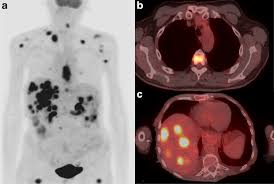

최첨단 현대의학으로 가장 적절한 방법이 양전자단층촬영술(Positron Emission Tomography, PET)이라고 나는 생각한다. PET는 체내 대사 변화를 촬영하는 기기로 CT나 MRI 다음에 개발된 영상장비이라고 한다.

요즘은 여기에 CT를 붙여서 PET 영상과 CT 영상을 융합해 서로 약점을 보완해 검사의 질을 더욱 높이고 있다고 한다.

여기에 방사성 핵종 F-18를 붙여(F-18 FDG라고 함) 혈관 주사하면 빨리 자리는 암세포는 포도당이 더 필요해 정상 세포보다 10∼100배 더 많이 모여들고 이를 방사능으로 촬영해 찾아낸다. 암이 1㎝만 돼도 10조개의 암세포가 있어 CT, MRI 소견이 애매한 경우 유용하게 쓰인다.

PET의 또 다른 장점으로 거의 모든 종류의 암을 찾아낼 수 있다는 것이라고 한다. 일반적으로 암세포는 포도당 대사가 높기 때문이라고 한다.

또 머리끝에서 발끝까지 촬영해 어느 곳에 있는 암이라도 잡아낸다. 다시 말하면 사각지대가 없다고나 할까? 이미 일본에서는 이 방법으로 암을 검진하는 프로젝트를 성황리에 진행하고 있다고 한다.

그러나 일본의 경우 증상이 없는 PET 검진자의 1∼2%에서 암을 찾아내고 있다고 한다. 또 이미 암을 진단받은 후에도 전신 PET를 해 보면 5∼7%에서 숨어 있는 다른 암을 찾을 수 있다고 한다.

물론 고령의 할아버지와 할머니가 많지만 우리나라 남자의 3분의1에서 2분의1이 일생동안 결국은 암에 걸린다는 통계자료를 볼 때 수긍이 된다. 일본 자료에 의하면 갑상선암, 폐암, 대장암 등이 잘 발견되고 있다고 한다.